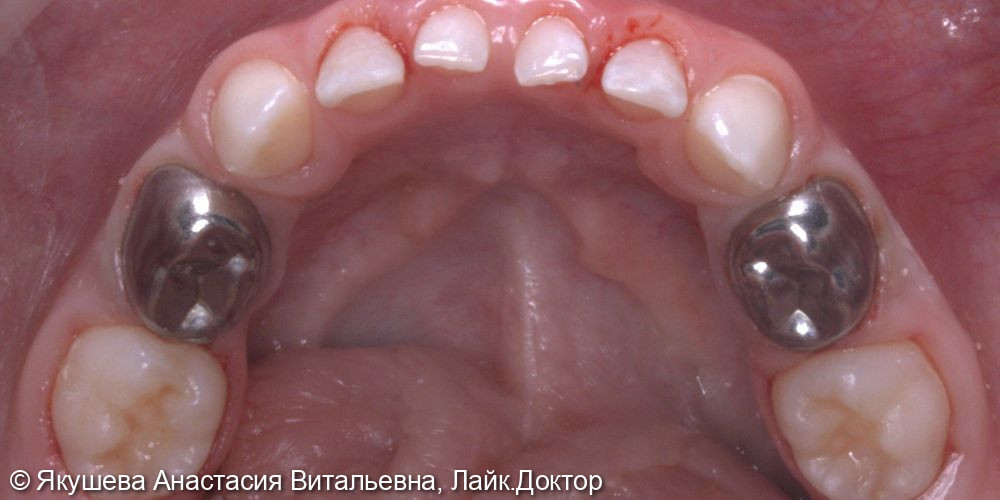

55;54;64;85;84;74;75 : К04.0 Пульпит (K04.0 Пульпит)

55;54;64;85;84;74;75 : в условиях общего обезболивания: очищение мягкого зубного налета, изоляция коффердам, проведено препарирование кариозной полости, раскрытие полости зуба, проведена пульпотомия, достигнут гемостаз,Показать полностью...